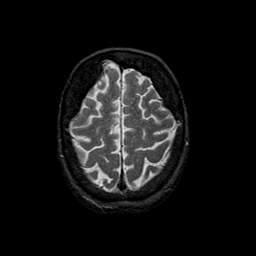

Tour 1: Next/Previous/Start: This tour will examine the brain of an elderly woman with Alzheimer's disease. This brain displays many of the commonest features of the disease: brain shrinkage, or atrophy, and loss of function, as indicated by hypoperfusion (described in Tour 2). First, look at the prominent sulci, especially the central sulcus. Some reduction in brain volume is a part of normal aging, but compare this brain with the normal central sulcus, from a normal 81 year old woman. The abnormal shrinkage seen in this case, while not a finding specific to Alzheimer's disease, is severe and seems to affect some regions more than others.